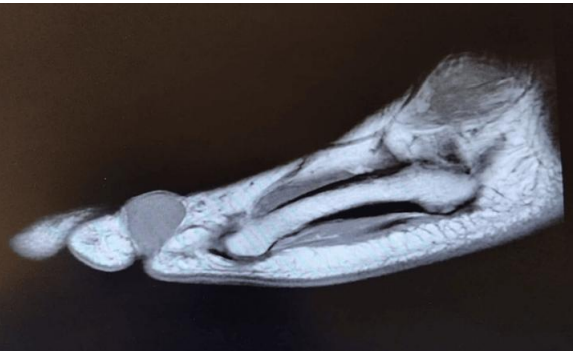

MRI: Revealed an oval-shaped mass on the medial and dorsal aspect of the fifth toe's proximal phalanx, measuring approximately 2 cm. It exhibited intermediate low signal intensity on T1-weighted images and mildly higher heterogeneous intermediate signal intensity on T2-weighted images, closely associated with the flexor tendon (Figures 1, 2 & 3)

FIGURE 3: MRI view of the foot demonstrating longitudinal soft tissue structures